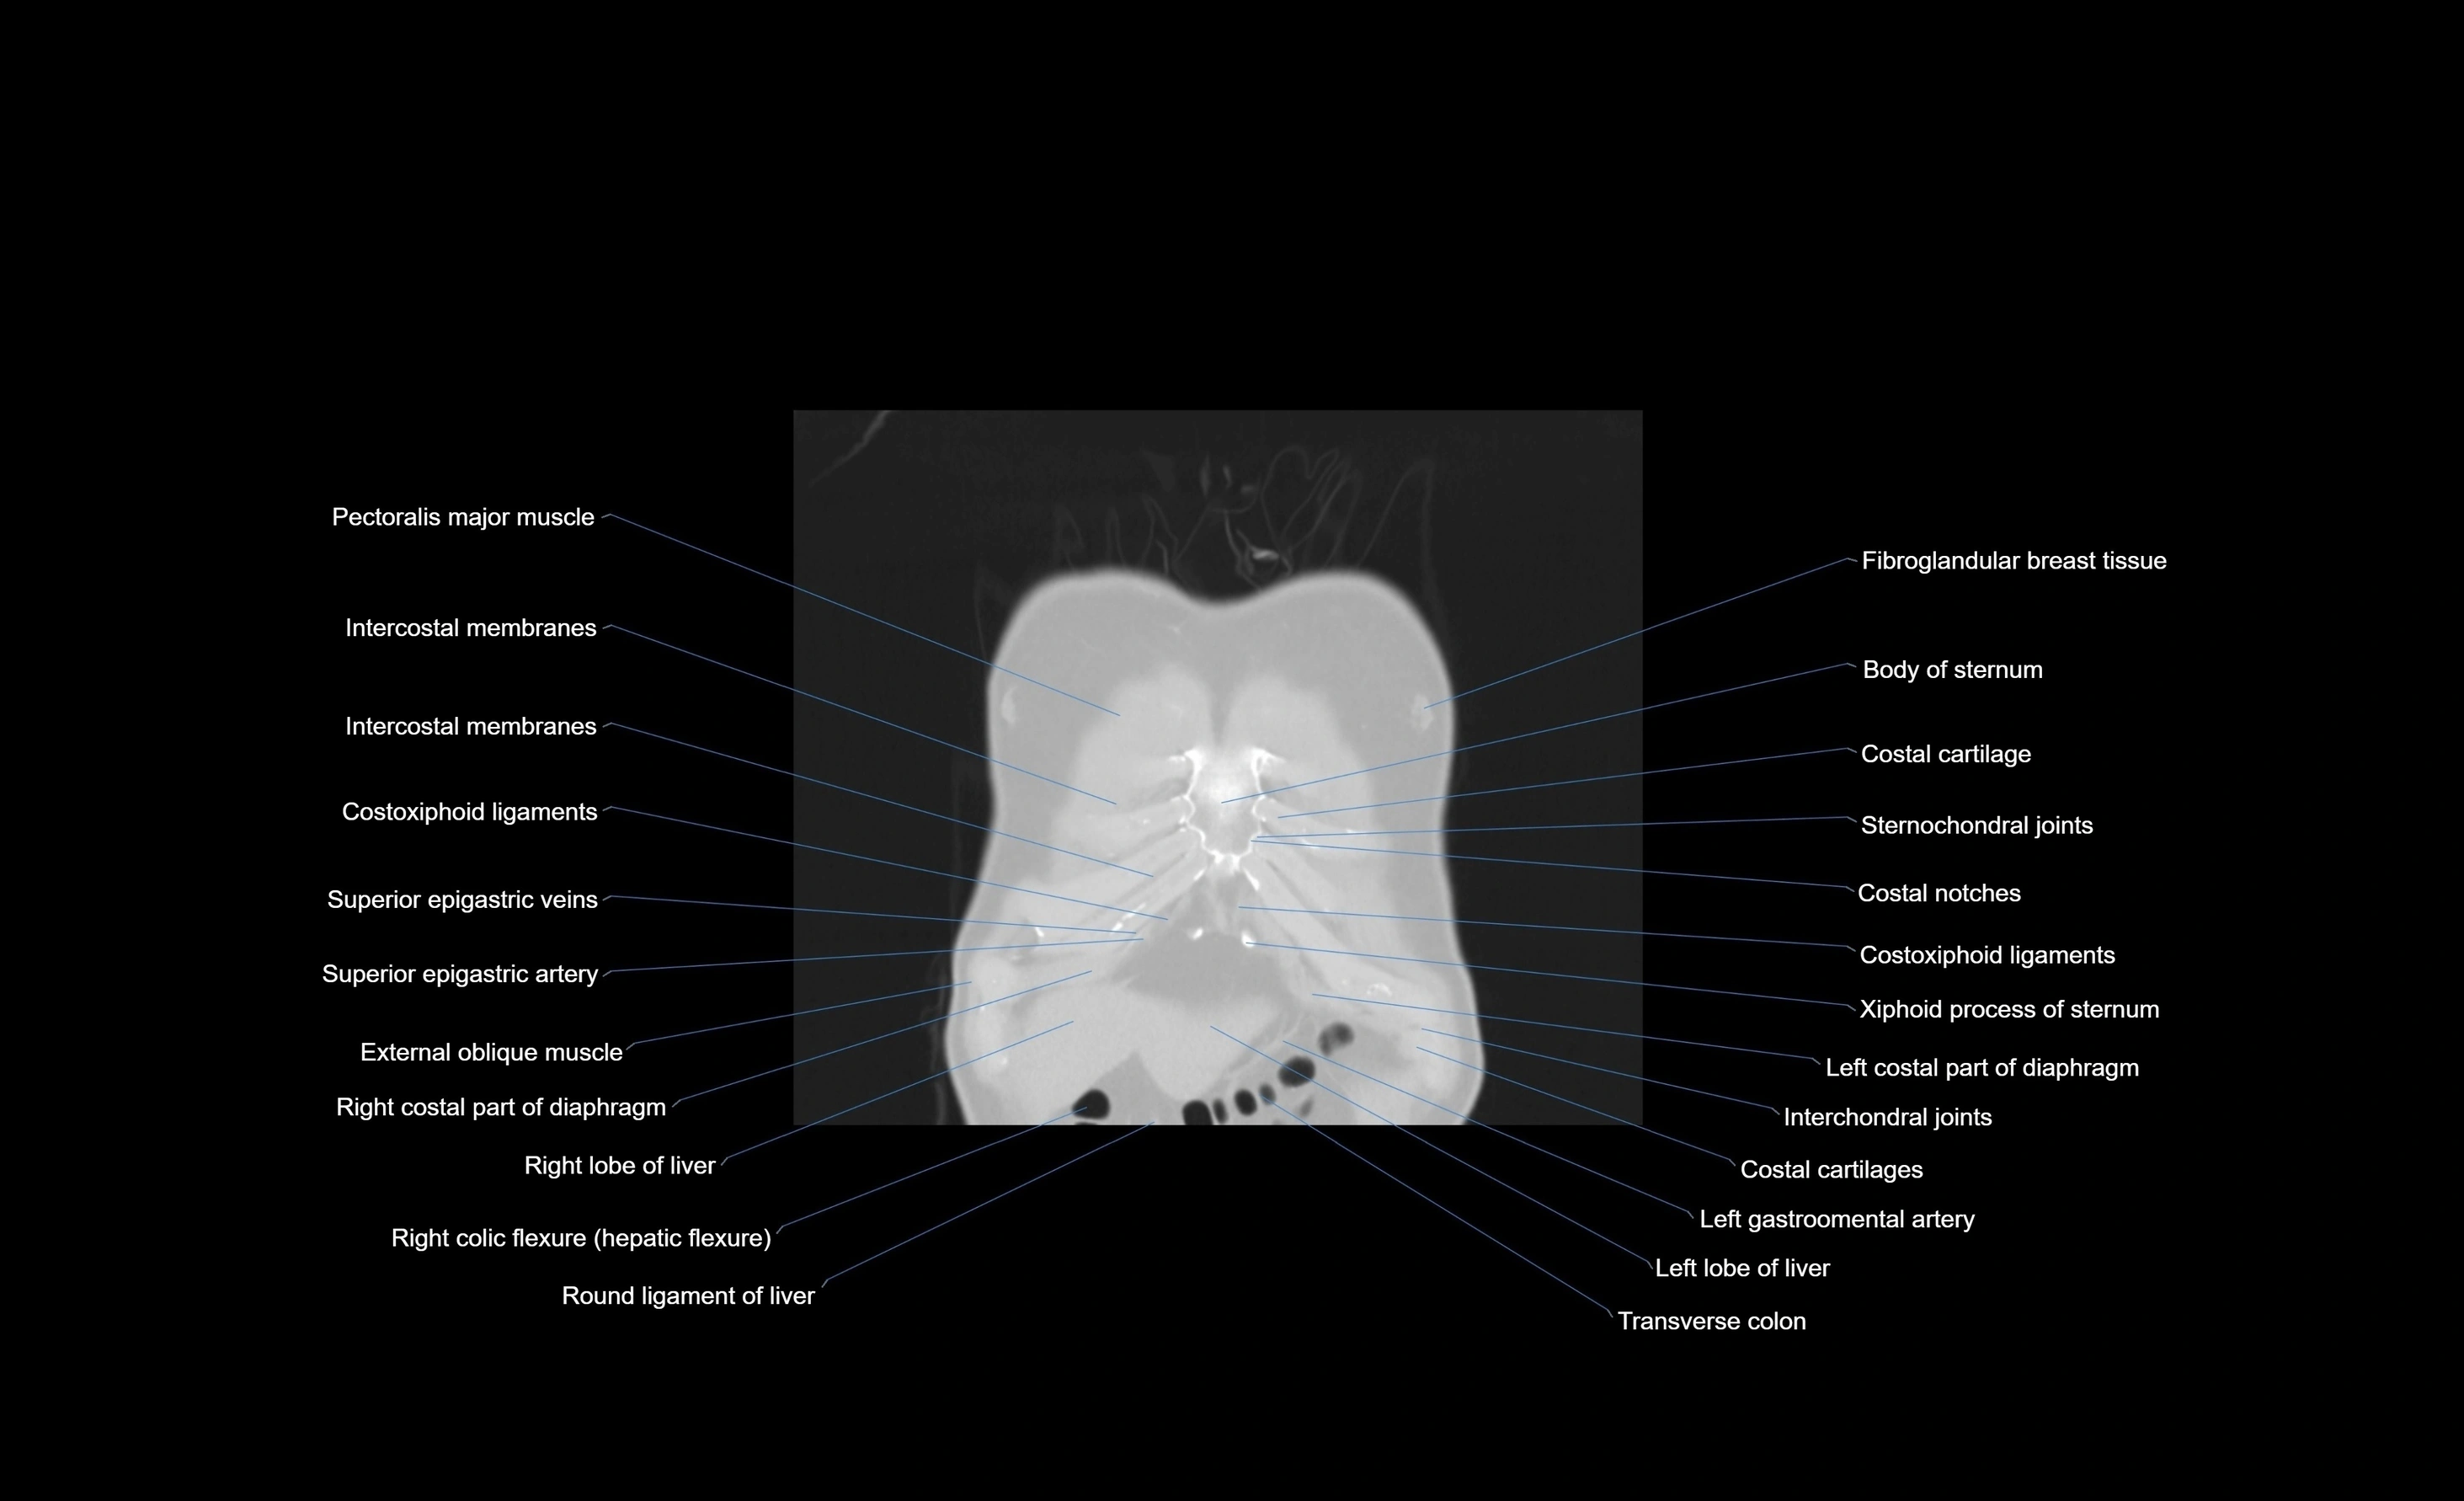

CT images